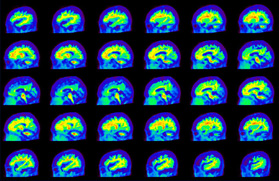

Head / Case4 : Amyloid

Sagittal

Courtesy : Kindai University Hospital

- Imaging protocol

- Injected dose: 3.21 MBq/kg, 18F-Flutemetamol

- Uptake time: 100 minutes

- Scan time: 20 minutes